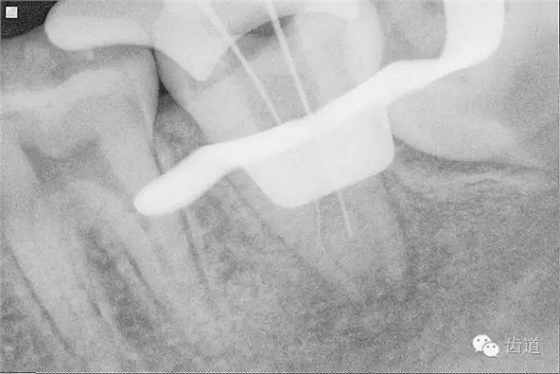

10. X線根尖片示尖 (近中及峽部)

17. X線主尖片